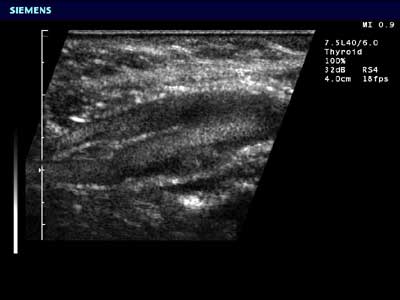

Рисунок. SieFlow от фирмы SIEMENS обеспечивает прямую визуализация кровотока в В-режиме на примере гемодинамики в сонной артерии.